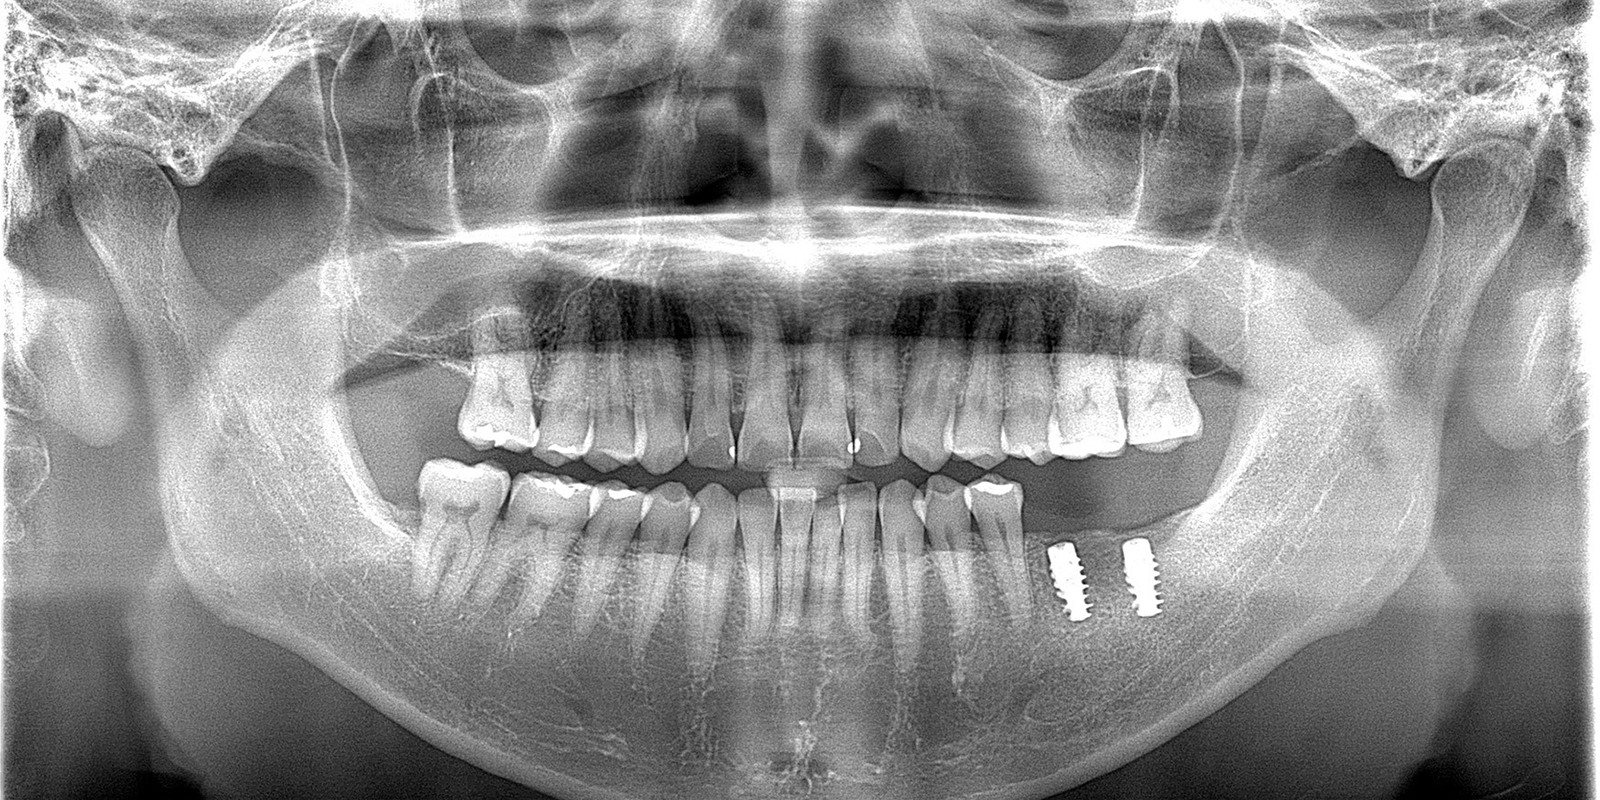

術後のレントゲン写真

また、当院ではインプラントメーカーを複数用意しており、そのそれぞれについて術式は異なります。今回使用したのは、ストローマンというインプラントメーカーのBLXインプラントです。